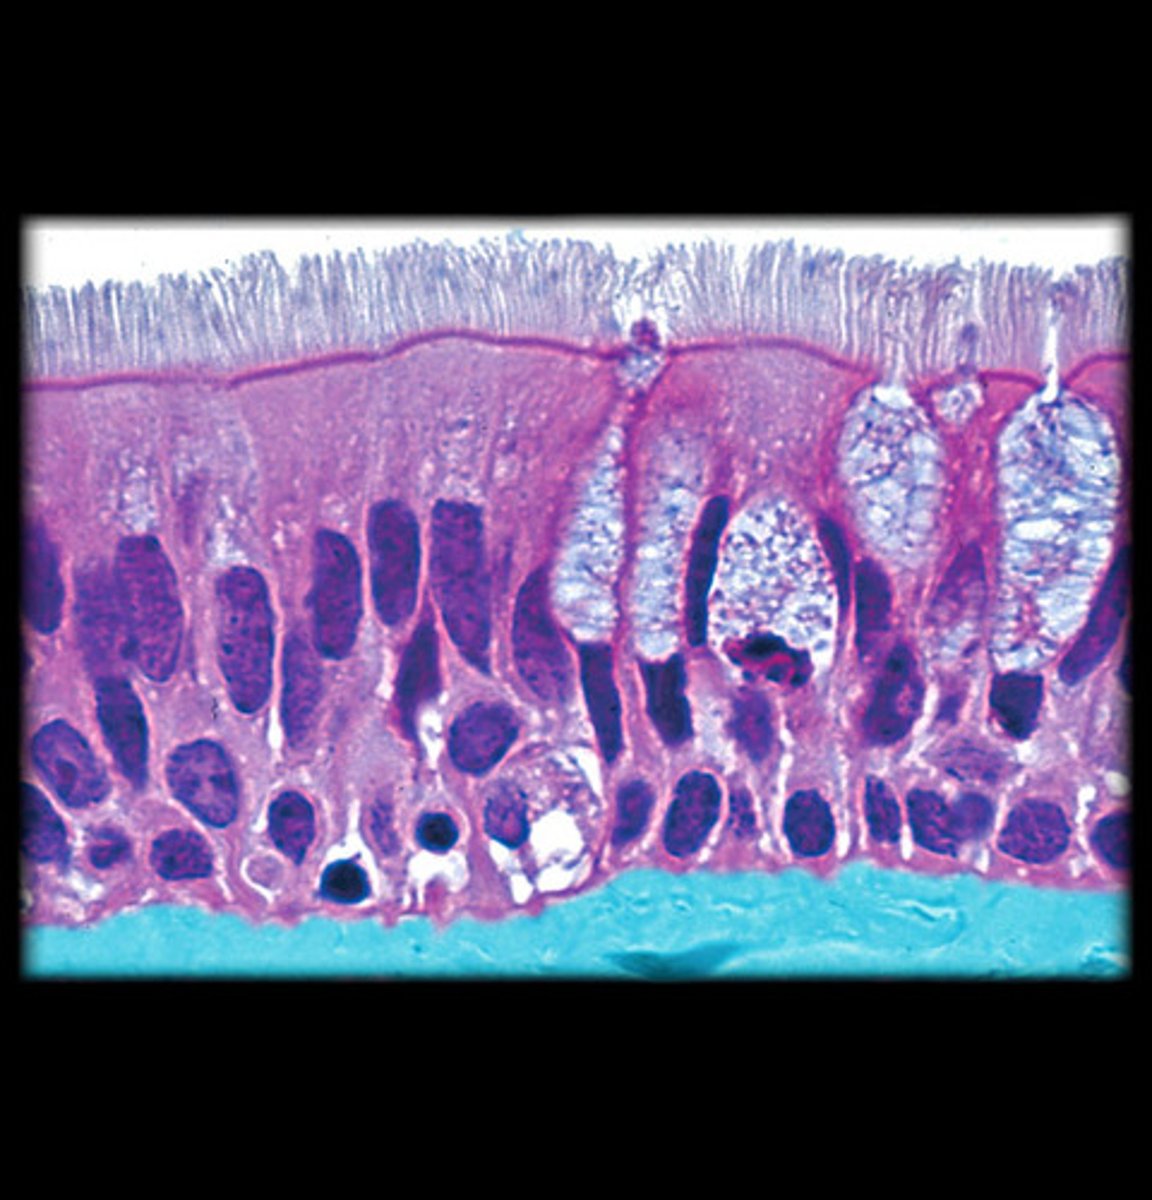

What type of epithelium is respiratory epithelium?

Pseudostratified ciliated epithelium.

What cell types are found in respiratory epithelium?

Ciliated, goblet, brush, small granule, and basal cells.

What is the function of ciliated cells?

Ciliary movement.

What is the function of goblet cells?

Mucus secretion.

What is found on the brush border?

microvilli

What is the function of small granule cells?

Secretory/endocrine.

What are basal cells?

stem cells for renewal of other cells

What cells are found in the lamina propria?

Fibroblasts, lymphocytes, plasma cells, macrophages, eosinophils.

Pseudostratified ciliated epithelium -> stratified squamous epithelium (image is at the vestibular folds)

What epithelium covers vestibular folds?

Respiratory epithelium.